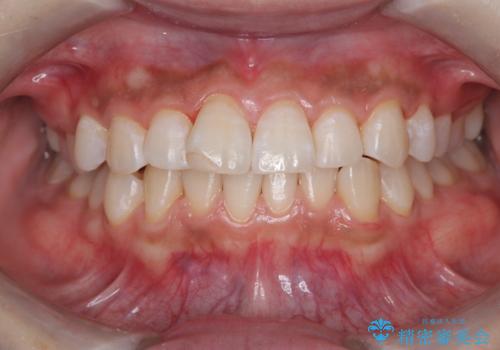

PMTC60分コースを行いました。

ステインとプラークが内側外側にとても多く付いていました。

タバコも吸うそうで、ステインが多かったです。60分コースでもギリギリ終わるくらいの汚れの量だったため、定期的にクリーニングやメンテナンスを行うようにおすすめしました。